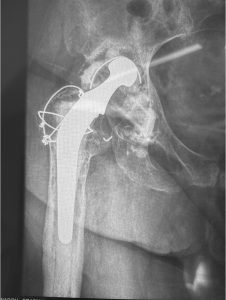

Πρόκειται για επεμβάσεις αναθεώρησης/revision των αρθροπλαστικών με τις οποίες γίνεται αφαίρεση μέρους ή όλων των αρχικών προθέσεων και αντικατάσταση με καινούργιες προθέσεις.

Κάθε περίπτωση έχει ιδιαιτερότητες που σχετίζονται με το είδος της αρθροπλαστικής που πρέπει να αναθεωρηθεί, με τον τρόπο που θα αφαιρεθούν οι παλιές προθέσεις, με την τεχνική κάλυψης των οστικών ελλειμάτων που συνήθως υπάρχουν στην περιοχή, με τον τρόπο που πρέπει να στερεωθούν τα καινούργια υλικά, με τον χειρισμό των μαλακών μορίων κ.α.

Στις περισσότερες περιπτώσεις η επέμβαση αναθεώρησης των αρθροπλαστικών δεν έχει καμία σχέση με τις τεχνικές και τα υλικά που χρησιμοποιούνται στις αρχικές αρθροπλαστικές.

Η απαραίτητη εμπειρία της χειρουργικής ομάδας που χειρίζεται αυτές τις δύσκολες περιπτώσεις πρέπει να συνδυάζεται με την χρήση σύγχρονων υλικών.